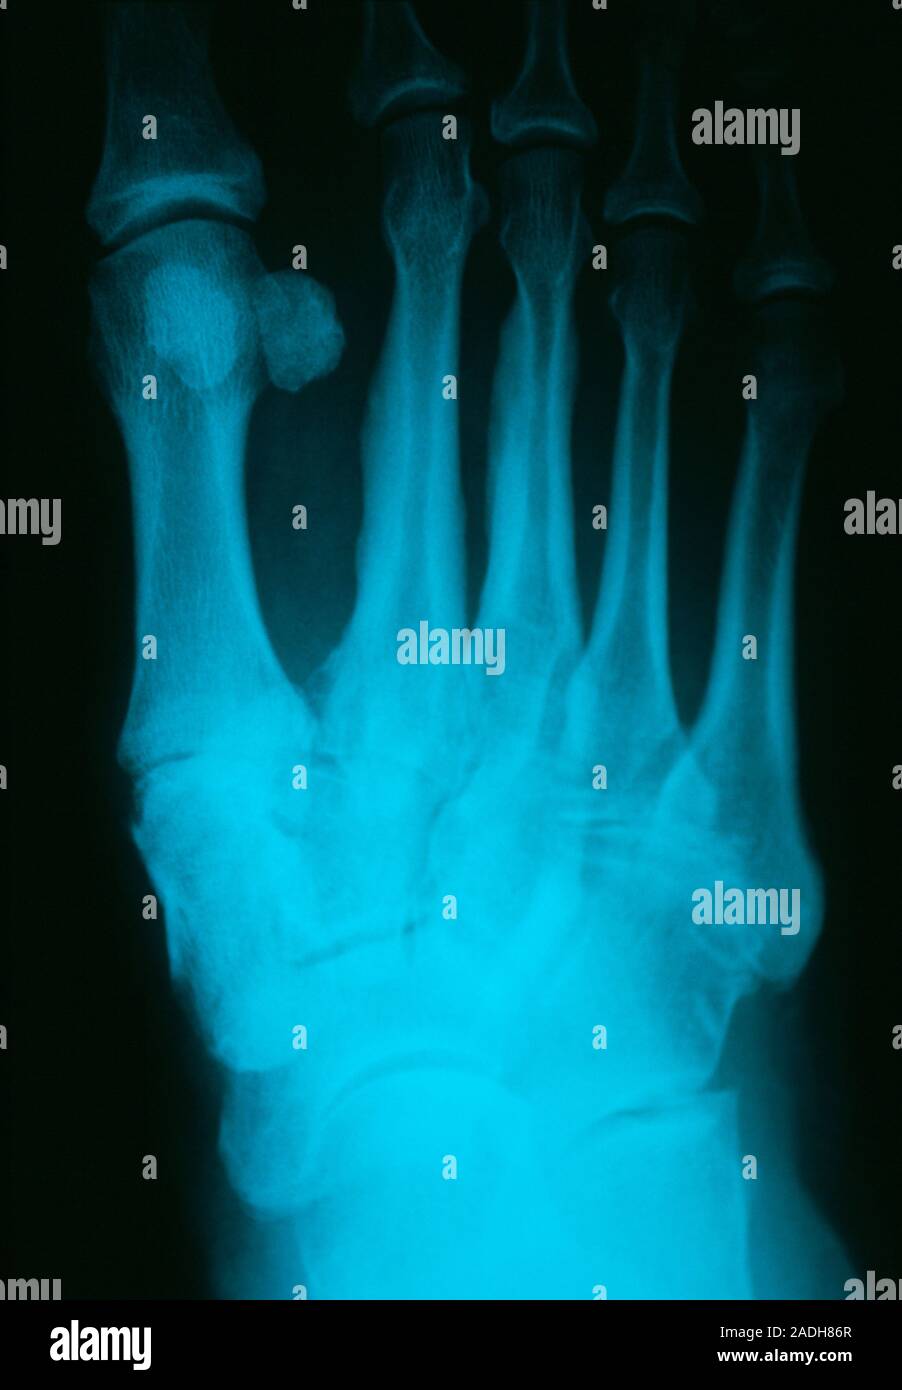

From www.alamy.com

Osteoarthritis of the foot. Xrays of the left foot of a 75yearold patient with osteoarthritis Osteoarthritis Big Toe Radiology what to know about osteoarthritis of the big toe (hallux rigidus) symptoms. a hallux valgus (plural: after reading the article and taking the test, the reader will be able to: osteoarthritis of the big toe, also known as hallux rigidus, can cause pain, stiffness, and loss of joint mobility. although imaging is not needed to. Osteoarthritis Big Toe Radiology.